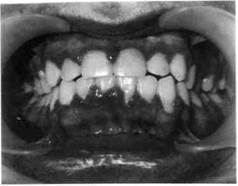

Хронический катаральный гингивит может возникнуть не только вследствие микробного налета, но и других местных причин — дефектов пломбирования и ортодонтического лечения, аномалий прикуса, прикрепления уздечек и тяжей слизистой оболочки, коротких уздечек губ, мелкого преддверия полости

рта, кариозных полостей придесне-вой локализации, изменения состава и уменьшения количества ротовой жидкости, а также различных видов травм (рис. 8.1).

Рис. 8.1. Хронический катаральный гингивит.